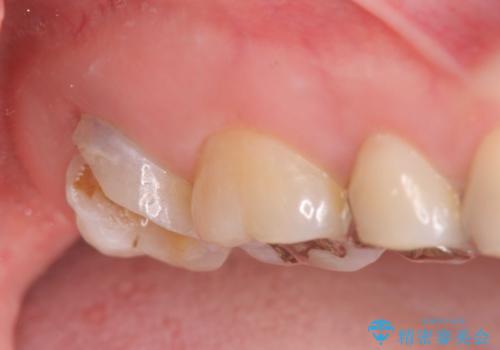

放置した虫歯を外科を行い抜歯を回避

- 放置していた虫歯が欠け、いよいよ怖くなり治療を希望され来院されました。

虫歯は、その進行度によりさまざまな治療法が提案されますが、

エナメル質・象牙質に限局する虫歯 →インレー修復

歯の神経に達する虫歯 →根管治療 クラウン補綴

歯ぐきよりも深い虫歯 →歯周外科による歯周環境の整備

を適宜行うことで良好な結果を得ることができます。